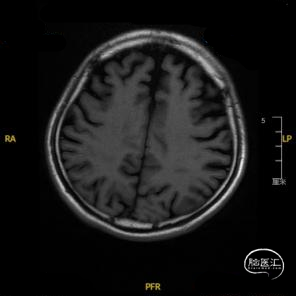

➢ 入院后头核磁检查

患者主因言语不利3天入院,头核磁提示右侧额、顶叶多发低灌注梗塞,脑血管造影提示右侧颈内动脉开口重度狭窄,为责任血管,另外患者前交通动脉、右侧后交通动脉开放不良,并且狭窄严重,考虑到高灌注风险,决定分期处理,一期小球囊扩张改善供血,二期支架成型。